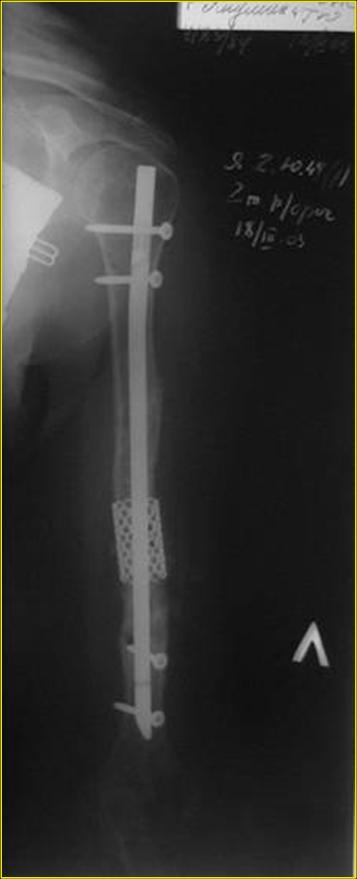

Рентгеновская версия реконструкции хронология в обратном порядке: 1,2

- через 1 год, 3,4 - 2 мес. после операции, 5,6 - после операции.

Движения в полном объеме востановлены к 2 мес. после операции. Если

надо могу  показать мультик. Сейчас уже прошло более 3 лет, больная не

показывается. Успехов ЛАФ.